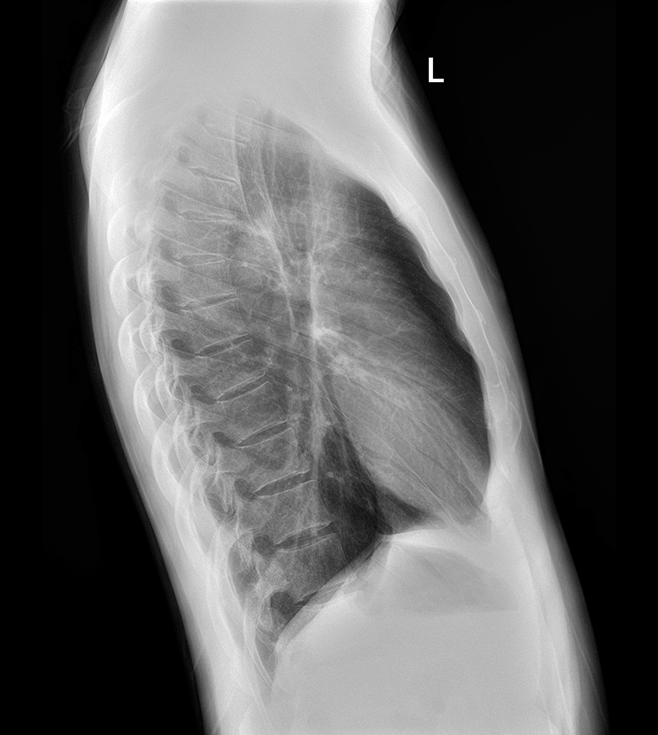

多功能诊断专用动态DR

太阳成集团tyc122cc入口科技全新设计的第四代床式动态DR,集拍片、透视、造影、全身拼接、尘肺体检于一体,一机多能,真正意义上实现全科室应用,提升医院实际效益。

高清动态平板探测器

搭载自主研发超清大视野动态平板探测器,600微米碘化铯大幅提升X线转化效率,独特的非晶硅阵列与高速读取集成电路紧密协作,轻松实现多帧率透视与高清点片。

专业的影像处理系统

“腾灵”系列搭载的IEAE影像处理系统,具备多项发明专利。本系统采用多频域图像处理技术,其6大核心处理模块使影像具有优秀的一致性、柔和性、空间层次感和纹理细腻度,为用户精准诊断病灶奠定了坚实的基础。